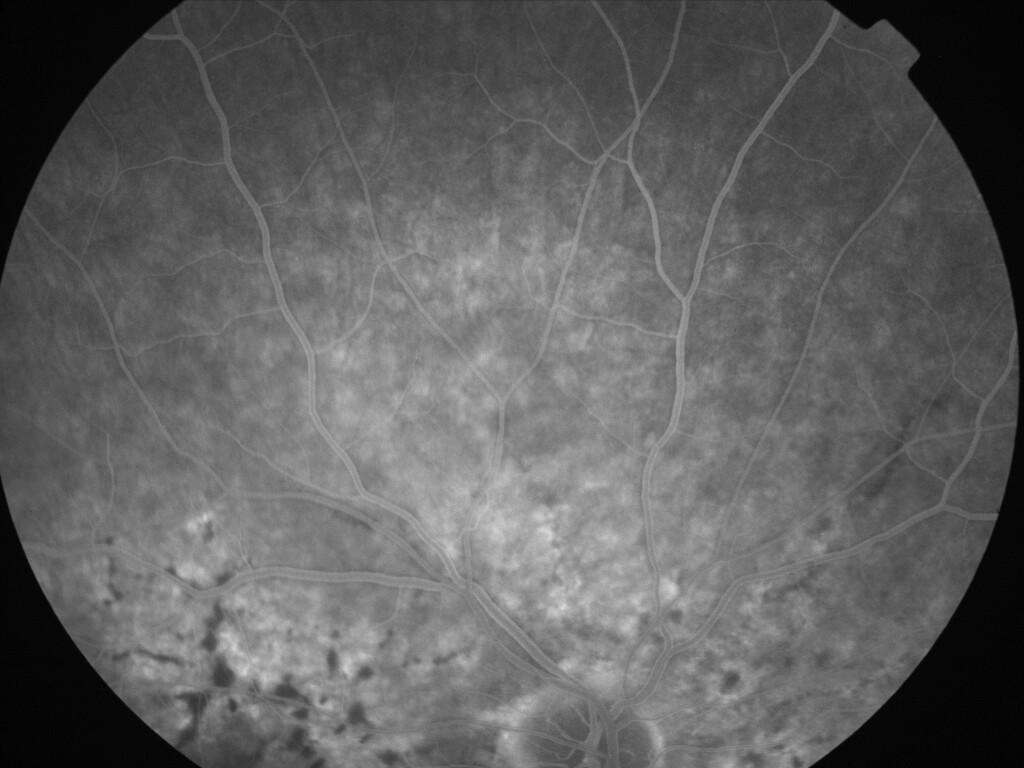

ASSOCIATION STRIES ANGIOIDES ET DYSROPHIE MACULAIRE RETICULEE

NEOVASCULARISATION